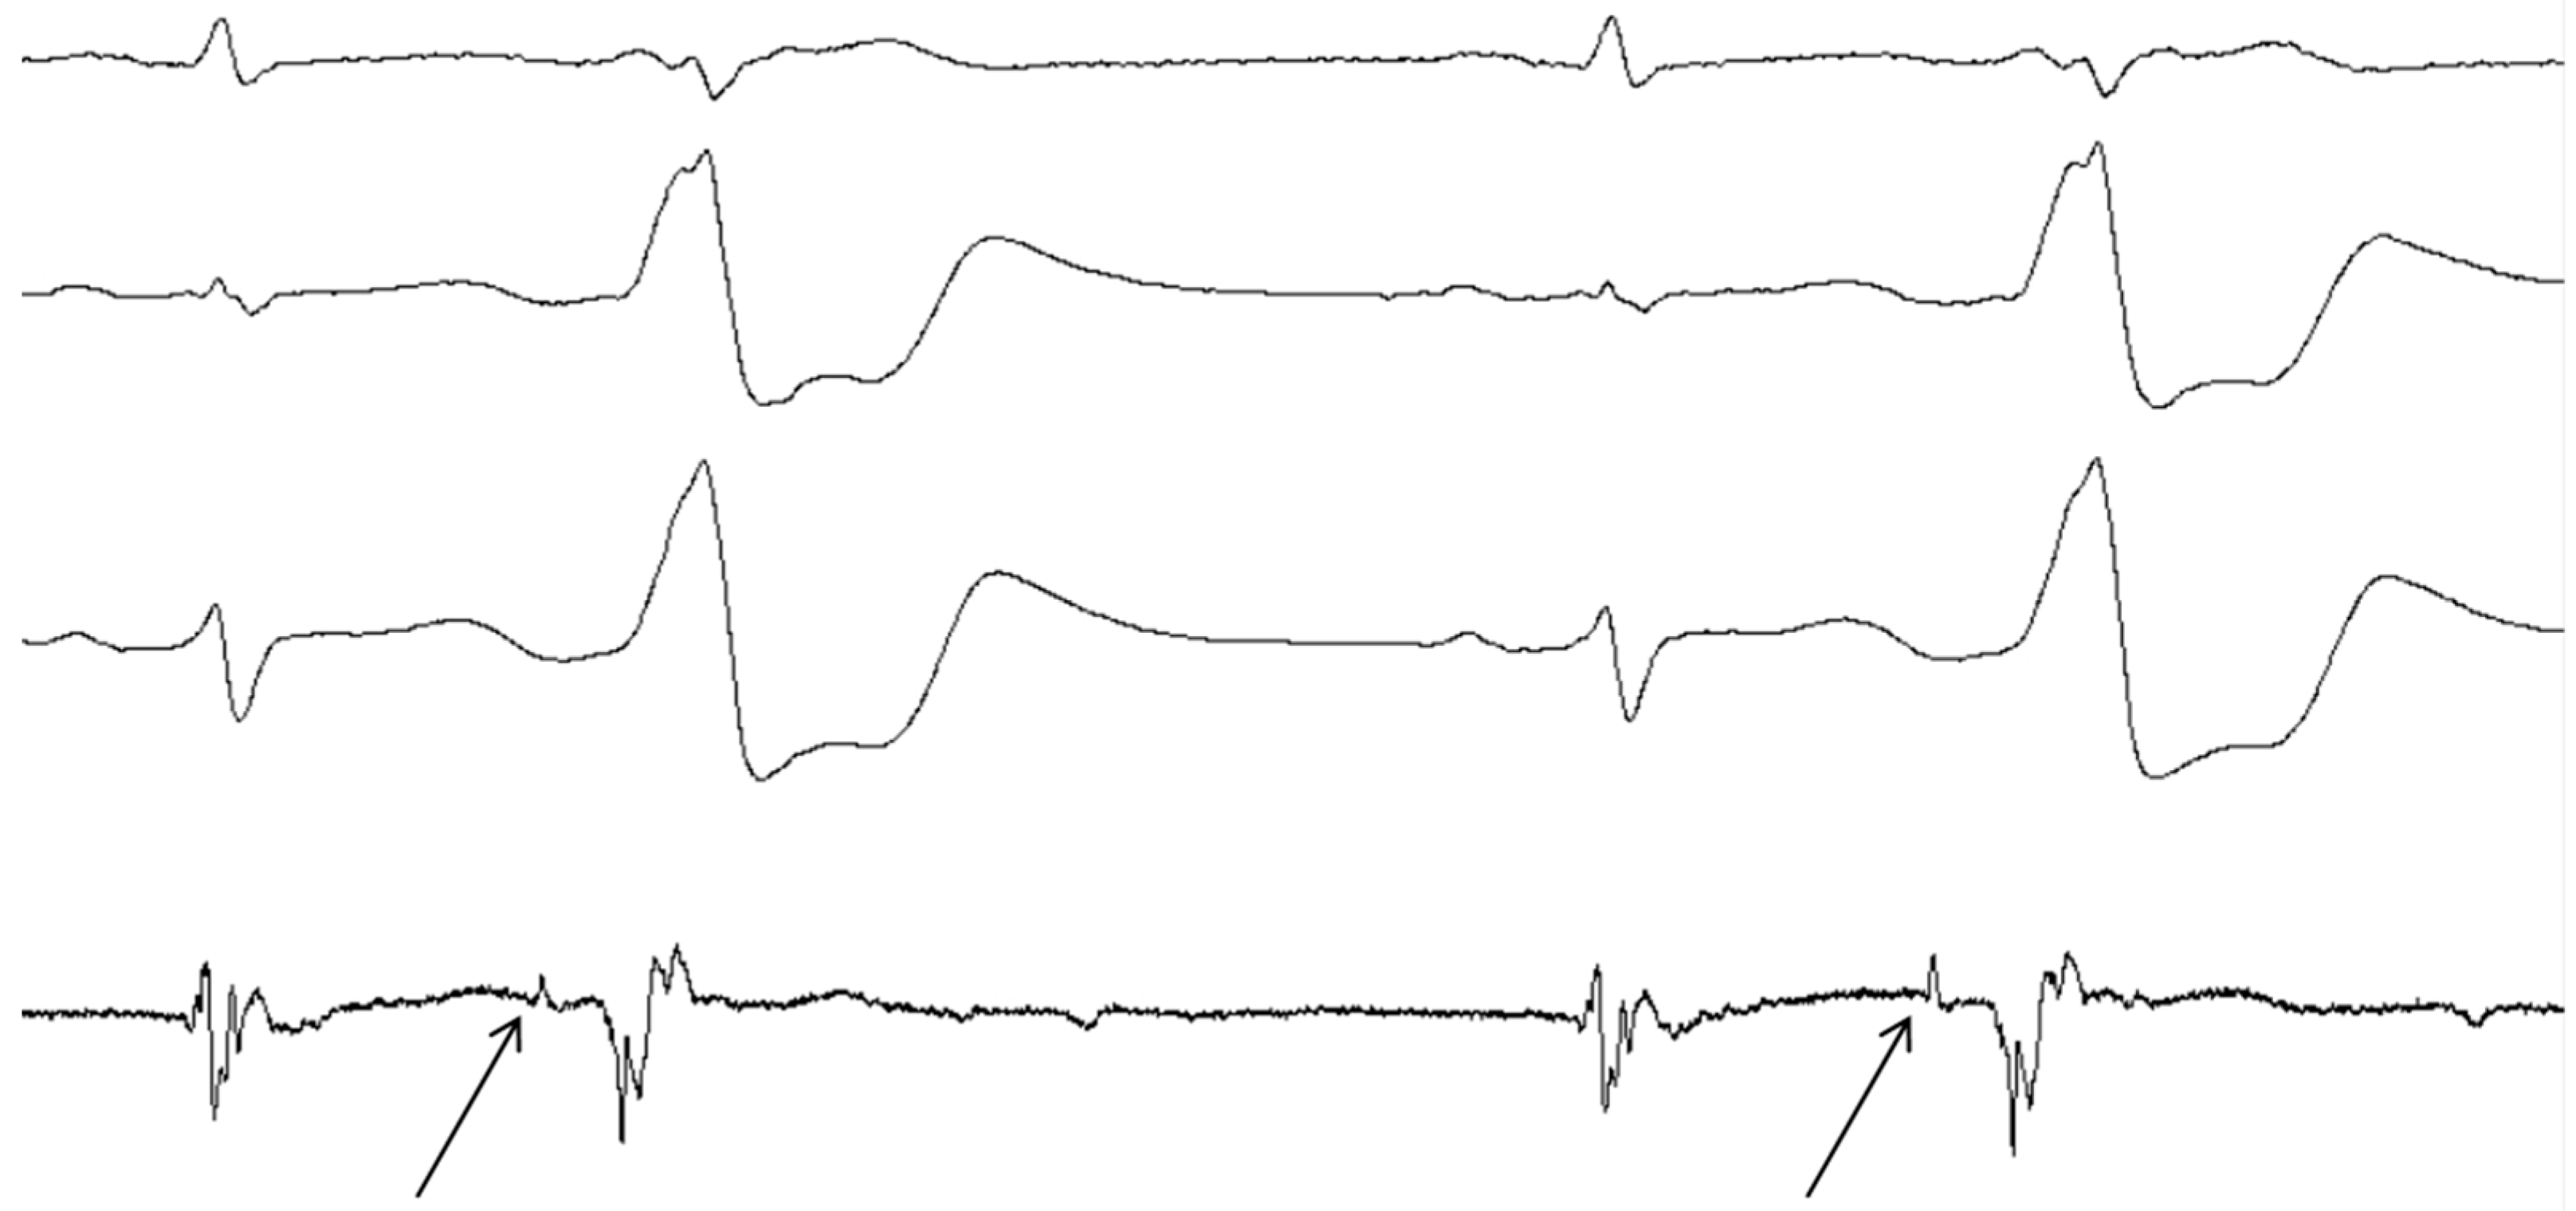

- McGuire, M.A.; de Bakker, J.M.; Vermeulen, J.T.; Opthof, T.; Becker, A.E.; Janse, M.J. Origin and significance of double potentials near the atrioventricular node. Correlation of extracellular potentials, intracellular potentials, and histology. Circulation 1994, 89, 2351–2360. [Google Scholar] [CrossRef] [PubMed]

- McGuire, M.A.; de Bakker, J.M.; Vermeulen, J.T.; Moorman, A.F.; Loh, P.; Thibault, B.; Vermeulen, J.L.; Becker, A.E.; Janse, M.J. Atrioventricular junctional tissue. Discrepancy between histological and electrophysiological characteristics. Circulation 1996, 94, 571–577. [Google Scholar] [CrossRef] [PubMed]